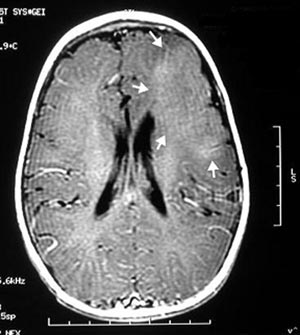

Figura 52 - Ressonância nuclear magnética pré-operatória.

Figura 54 - Ressonância nuclear magnética pós-operatória mostrando extensa ressecção frontal. Quando o paciente apresenta lesão extensa como esse caso, muitas vezes somente uma ressecção igualmente extensa deixará o paciente livre de crises.